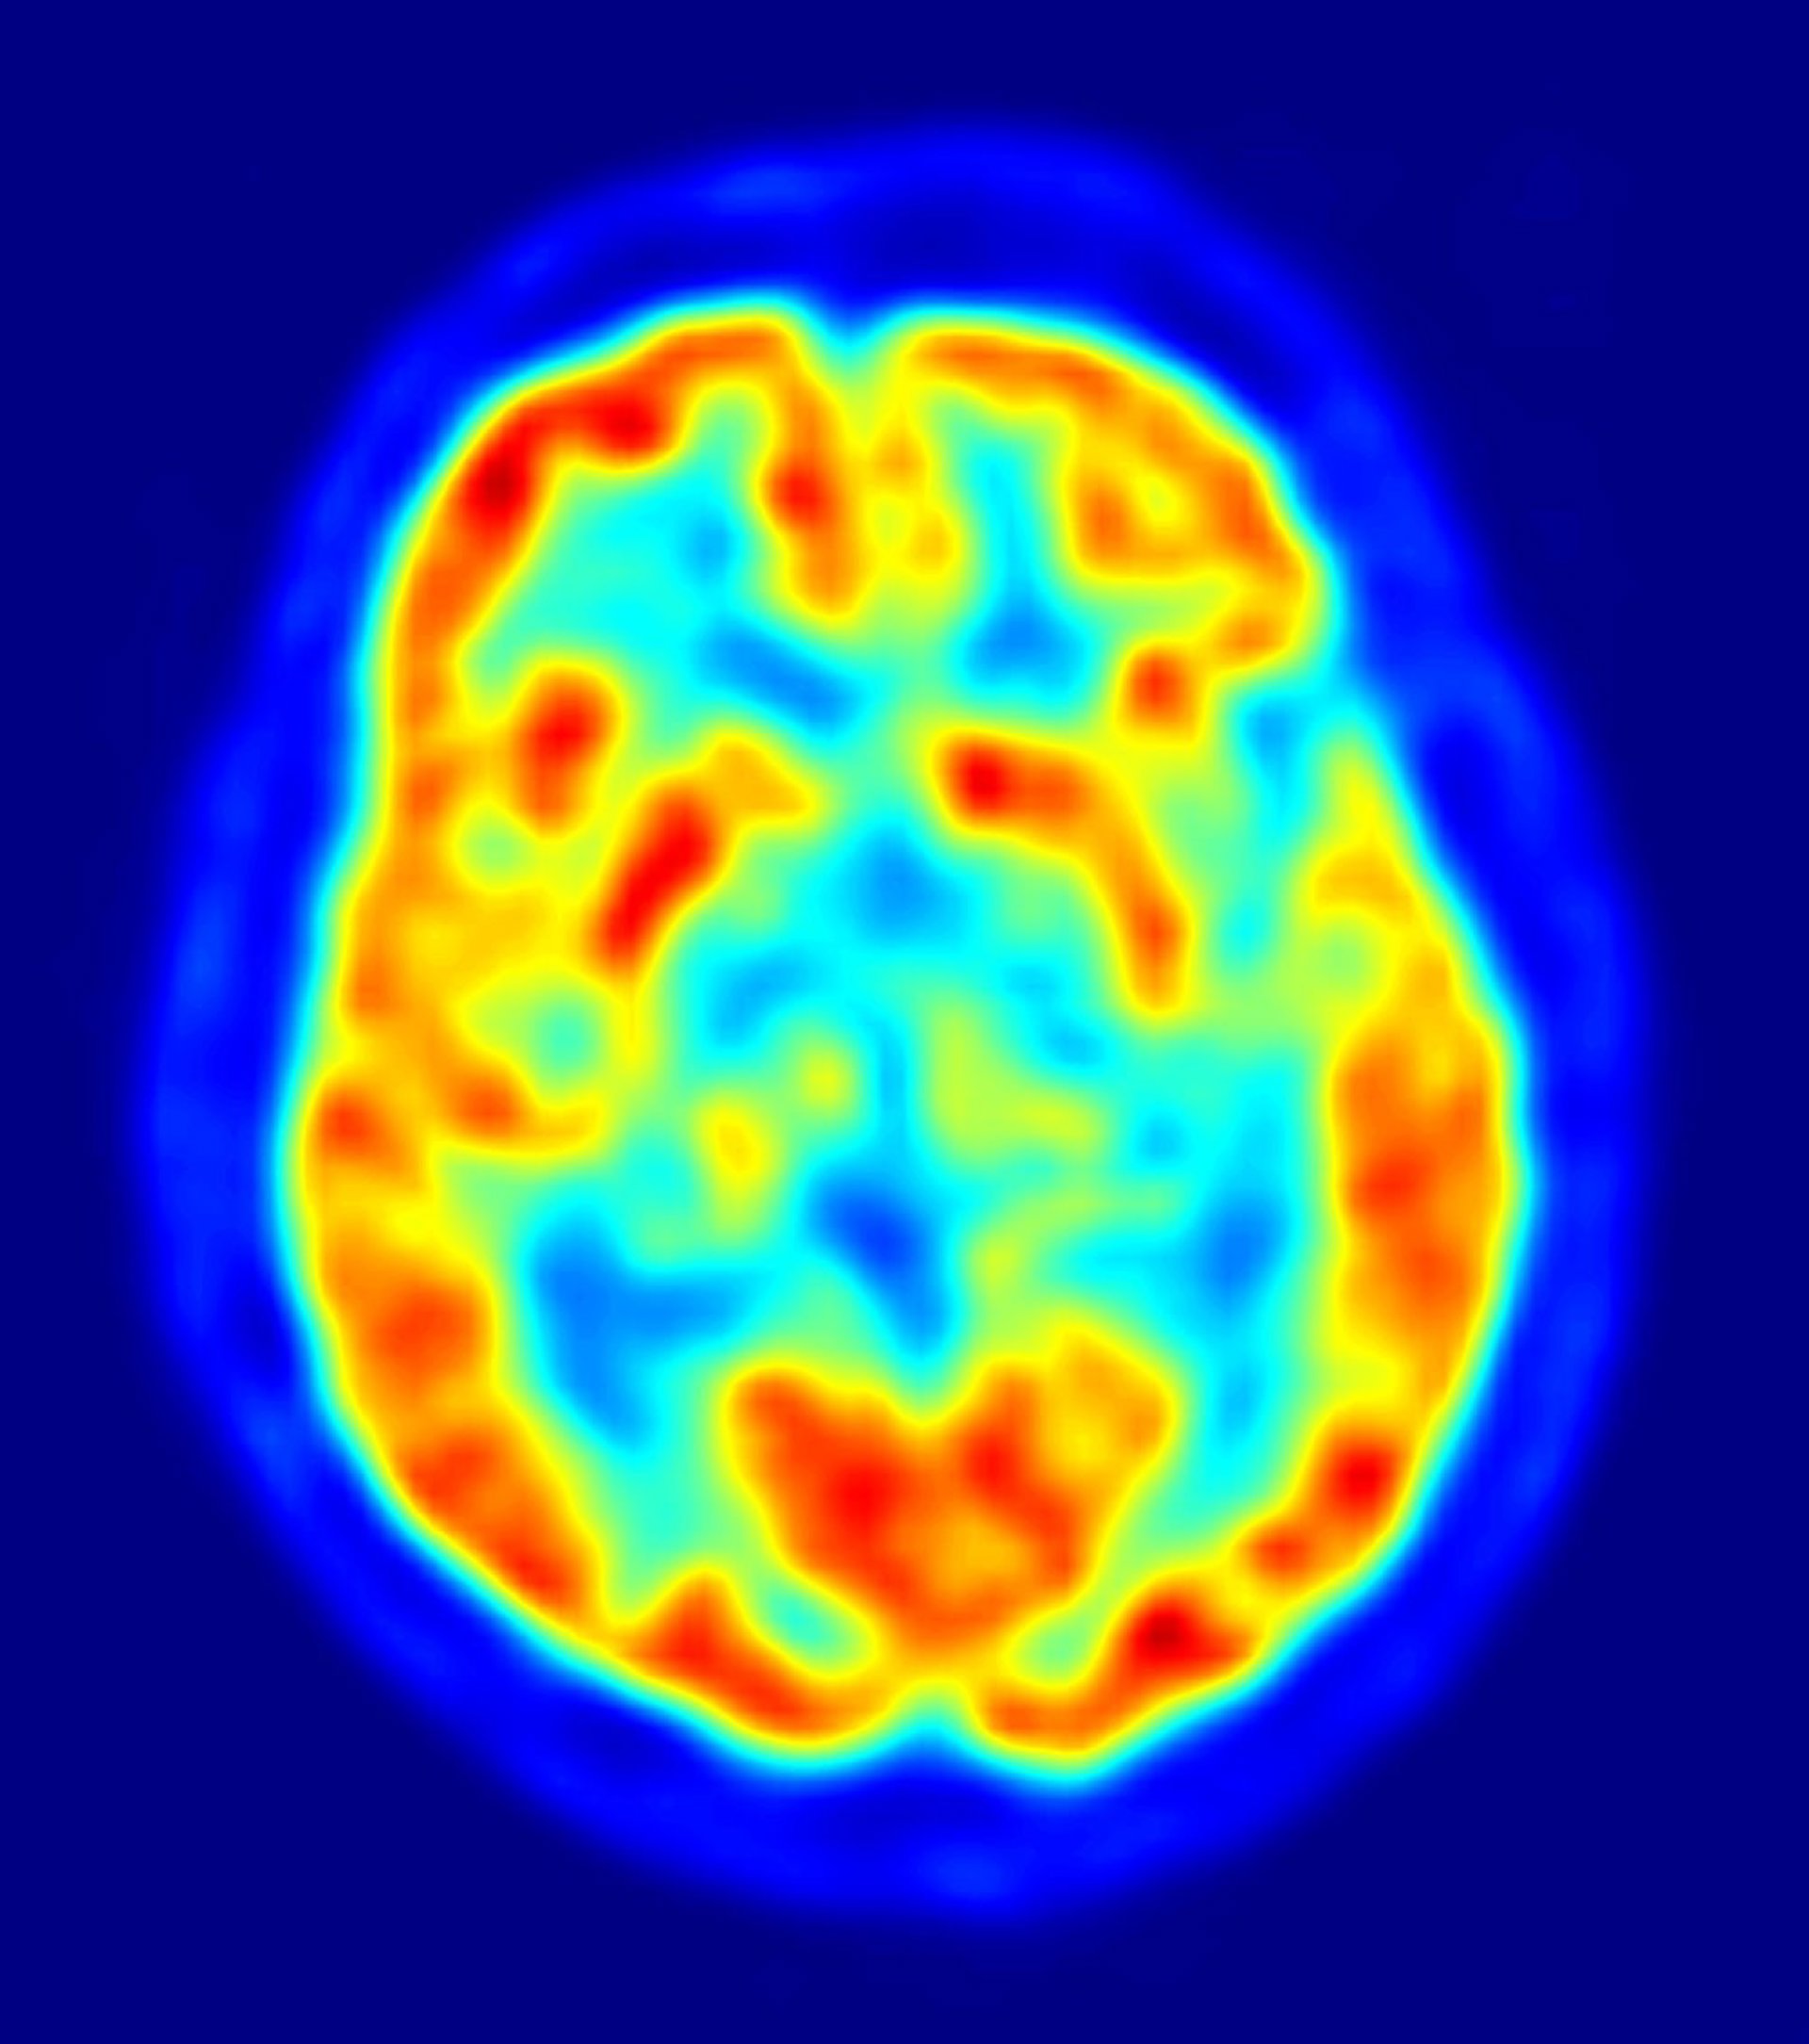

cerebro, recurso, neuronas

Investigadores del Centro de Circuitos Neurales Genéticos RIKEN-MIT han descubierto cómo las células cerebrales pueden recordar nuevos recuerdos y, al mismo tiempo, mantener los antiguos. Según los científicos, las neuronas específicas de una región del cerebro, llamada giro dentado, sirven distintas funciones en la formación de la memoria, dependiendo de si las células madre neurales que las produjeron eran jóvenes, o de edad avanzada.